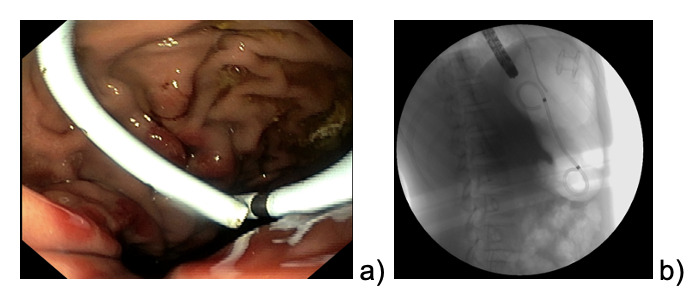

We describe the case of an 11 year-old female patient affected by pre-B ALL treated according to the early non-high-risk group in AIEOP-BFM-2017 protocol. One week after the start of Protocol Ia, a staging brain MRI showed cerebral venous thrombosis, which was treated with intravenous heparin for three weeks, followed by subcutaneous injections. The patient received two doses of PEG-asparaginases on days +12 and +26, and on day +48 she presented at the Emergency Department complaining of epigastric abdominal pain worsening after meals. Blood tests showed increased pancreatic enzymes (lipase 1383 U/l, amylase 310 U/l) and coagulation alterations (PT ratio 1,22, aPTT 1,09, Fibrynogen 111 mg/dl, Antithrombin 31%, D-Dimer 1087) suggesting acute pancreatitis, which was confirmed by a CT scan showing enlarged pancreas volume with multiple hypointense areas of necrotizing pancreatitis associated with local thrombosis of the distal splenic vein, and peritoneal and pleural effusions. A nasogastric tube was positioned and fasting started. After a few hours, her general conditions precipitated into a septic-like shock state, requiring fluid boluses, albumin, fibrinogen, antithrombin III, and broad-spectrum empirical antibiotics. Echocardiography showed mild pericardial effusion and signs of myocardial injury. The clinical and laboratory manifestations progressively resolved during the following days. After two weeks, an abdominal MRI revealed the initial formation of a non-encapsulated pancreatic fluid collection along the left side and hypochondrium, measuring 13 x 7 x 7 cm (Fig.1a).

The patient continued to refer mild abdominal pain, and a cholangio MRI confirmed the persistency of an encapsulated pancreatic fluid collection without size reduction (Fig.1b). After a multidisciplinary discussion, the decision was made to perform an endoscopic-ultrasound (EUS) guided cystogastrostomy with a 10 x 10 mm lumen-apposing metal stent (LAMS) (Hot-Axios™ system) under general anesthesia. During the procedure, after the release of the LAMS, a 7 cm x 7 Fr double-pigtail plastic stent (DPPS) was coaxially released (Fig.2); the post-operative course was uneventful and the patient was discharged after 48 hours. Seven days thereafter, an abdominal ultrasound confirmed the complete resolution of the PCF, the LAMS was removed, and a “soft” DPPS 7 cm x 10 Fr (Solus-Cook®) was positioned endoscopically in the cystic cavity under endoscopic and radiological control (Fig.3). The patient was dismissed the following day without any complications, and two weeks thereafter she restarted the AIEOP-BFM-2017 protocol at Short Consolidation B, 4 months after the interruption of the consolidation phase. No pancreatic fluid collection was observed at the following abdominal ultrasounds, the latest performed 7 months after interventions, together with an abdominal x-ray that showed the persistent presence of the double pig-tail. The prosthesis removal will be scheduled together with the central venous catheter removal at the end of the maintenance phase, due in a few months, so as to perform a single sedation.

_abdominal_mri_14_days_after_app__b)_cholangio_mri_3_months_after_app.png)